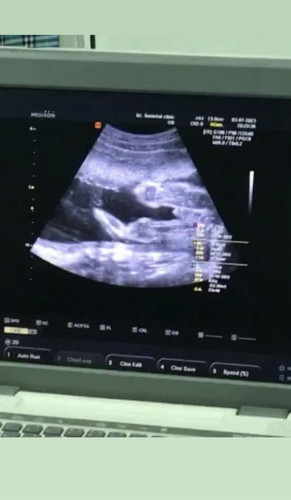

ท้องแรกค่ะ แม่ๆช่วยคอมเฟิร์มหน่อย

แม่ๆว่าผู้หญิงหรือผู้ชายชายค่ะ🥰

คิดว่าชายค่ะ มีไข่มีอะไรยื่นด้วย

เหมือนจู๋น้องโผล่เลยคะแม่